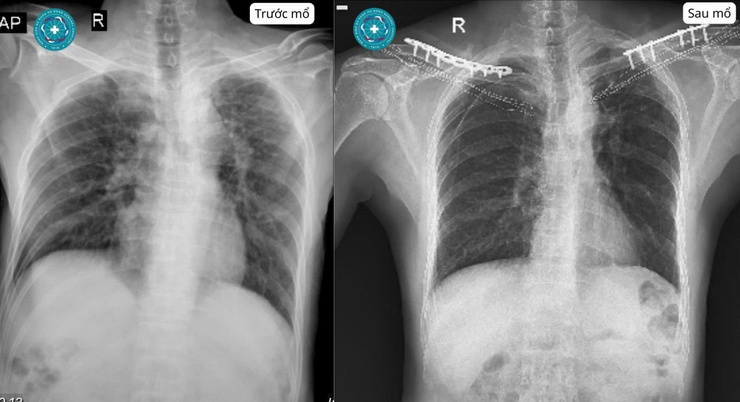

Mới đây, Bệnh viện đa khoa Hà Đông tiếp nhận nam bệnh nhân 59 tuổi (Vĩnh Tuy - Hà Nội ) được tiếp nhận sau tai nạn giao thông giữa xe máy và ô tô. Sau va chạm, người bệnh đau nhiều vùng hai vai, hạn chế vận động hai tay, vùng vai – đòn sưng nề và bầm tím rõ. Hình ảnh X-quang cho thấy bệnh nhân bị gãy xương đòn hai bên.

Bệnh nhân được chụp X - quang

Với dạng tổn thương này, điều quan trọng không chỉ là xác định ổ gãy mà còn phải đánh giá đầy đủ để tránh bỏ sót chấn thương phối hợp ở lồng ngực, cột sống cổ, khớp vai, mạch máu và thần kinh. Sau khi thăm khám, làm cận lâm sàng cần thiết và cân nhắc chỉ định điều trị, bệnh nhân được phẫu thuật kết hợp xương đòn hai bên.